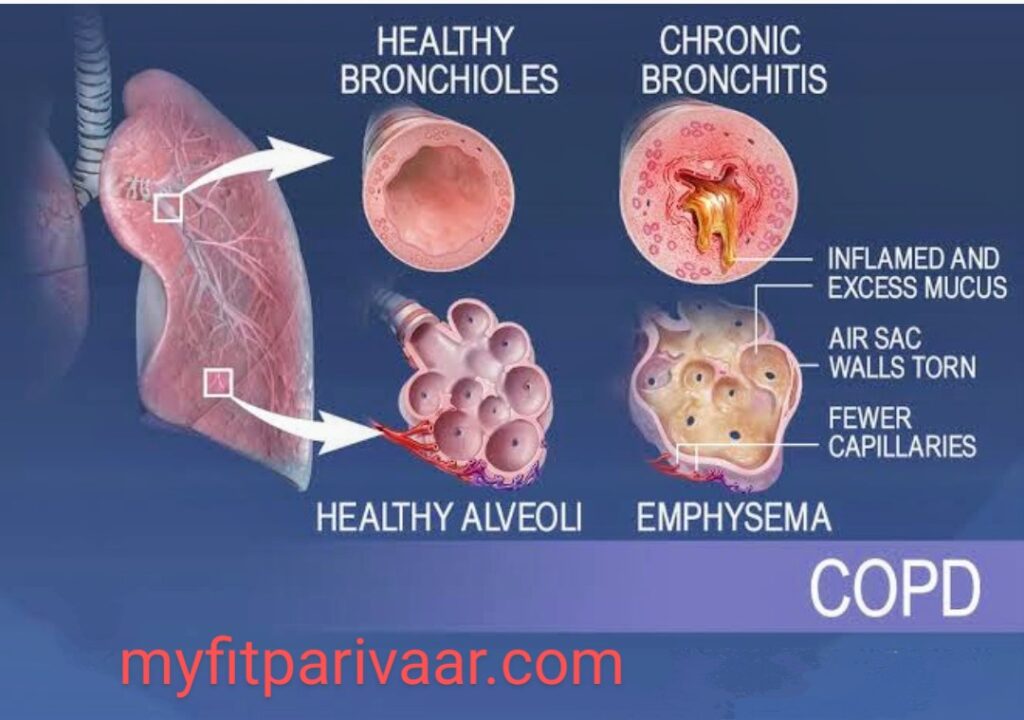

जिससे व्यक्ति को सांस लेने में कठिनाई होती है। ये सामान्य सर्दी-जुकाम से लेकर अस्थमा, क्रॉनिक ऑब्सट्रक्टिव पल्मोनरी डिजीज (COPD), निमोनिया, और फेफड़ों के कैंसर तक हो सकती हैं।आज हम श्वसन संबंधी बीमारियों पर चर्चा करेंगे, जो दुनियाभर में तेजी से फैल रही हैं। क्या आप जानते हैं कि हर साल लाखों लोग इन बीमारियों से प्रभावित होते हैं?

जिससे व्यक्ति को सांस लेने में कठिनाई होती है। ये सामान्य सर्दी-जुकाम से लेकर अस्थमा, क्रॉनिक ऑब्सट्रक्टिव पल्मोनरी डिजीज (COPD), निमोनिया, और फेफड़ों के कैंसर तक हो सकती हैं।

अस्थमा और COPD के मरीजों में सांस लेते समय सीटी जैसी आवाज आ सकती है, जो वायु मार्ग में रुकावट का संकेत है।